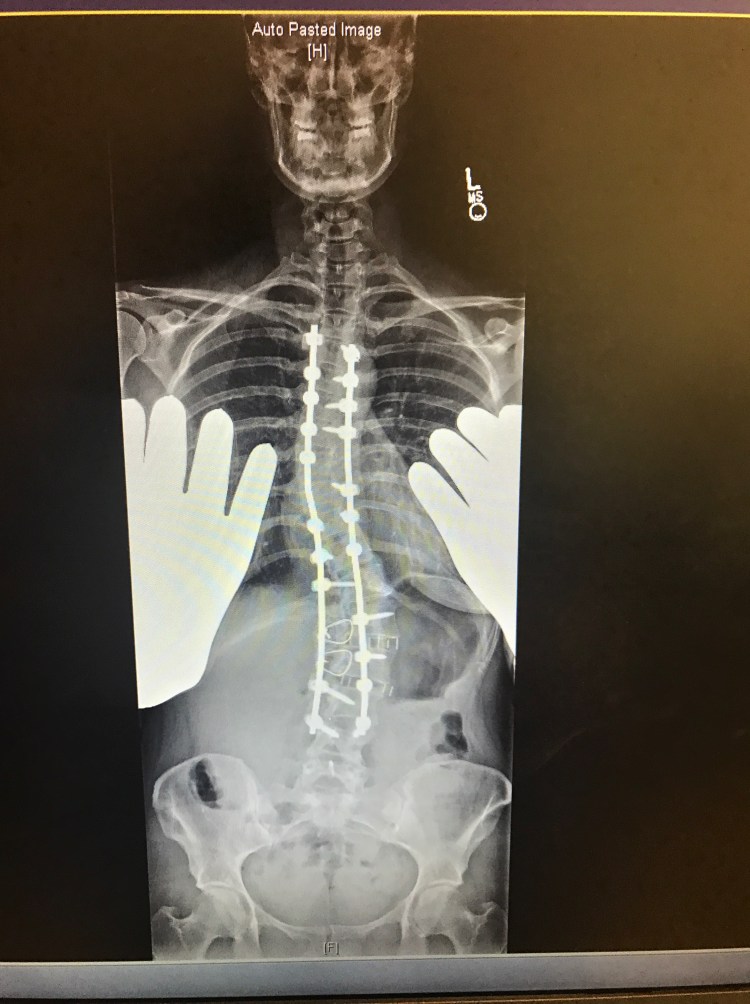

Last week, on Will’s birthday, it was also my 5 month post op appointment. I had a long list of questions and concerns and I was extremely anxious. These appointments always make me nervous and give me anxiety. While in the car on the long drive there, I can’t help but think about everything that happened and how it is going to affect me for the rest of my life. The feeling of these long rods screwed into my spine will never go away although hopefully get easier to forget about over time. I will never be able to bend my back or twist or bend side to side EVER. I still get asked this on a daily basis. The answer is never. Then, I have to continue to be cautious and not slip or fall or do anything that could cause a screw or rod to break and hope upon hope that these rods and screws can last the duration of my life without needing to be replaced. I already know somewhere in the future I will need another surgery to fuse the last few levels to my pelvis and boy am I already dreading for that day to come. Sorry to be a Debbie Downer. I guess it’s hard when people think because I am back at work, or can drive Will to preschool or wrap some damn Christmas presents that I must be “better”. Anyways…..my Doctor said that my bones are fusing. One side is fusing better than the other, but she is hopeful that the other side will catch up. She thinks that the first few months and all the added stress on my body prohibited me from really recovering until just recently. Fusions also can take up to 2 years from surgery to heal completely. All my screws are in place as well. We agreed I need to continue with physical therapy. Last week, I began light core muscle exercises with some resistance to help build my stomach muscles back up. Right now, I am having trouble standing up all the way do to the tightness in my hips and hamstrings. When I am not standing straight, it causes my back muscles to fire up causing some pretty crappy back pain. There’s still a long way to go to get this leg working and my shoulder is still causing me trouble as well. I am also still having blackout and dizzy spells which we had attributed to medicine, however, since being off everything for the most part, I am still having these multiple times a day. I was told I need to see a neurologist and get a primary doctor to run some tests.

You look great. Your xrays look even straighter now!!! Do you live in Cali? Im trying to figure that one out because your dressed like its cold and i thought you lived in Cali. Who was your surgeon again.? God Bless. Your a strong woman and sounds like you have a great supportive husband.

Yes in Northern California. Our weather can be in the 100’s in summer and in the 30’s in Winter. My back is actually a little less straight than right after with settling, but definitely staying put and starting to fuse!